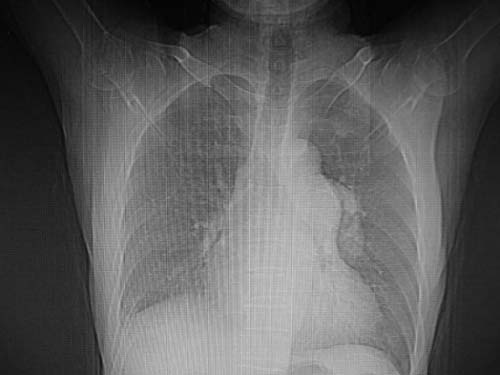

男,80岁

肺a高压征[左肺a狭窄?];肺,胸膜tb

1)考虑肺动脉狭窄。2)右肺上叶继发性肺结核。3)右侧胸膜增厚、钙化,左侧胸膜反应。

左肺动脉异常增粗,考虑肺动脉狭窄可能。

右肺上叶继发性肺结核。

右侧胸膜增厚、钙化,左侧胸膜反应。

双肺陈旧性病变,左肺动脉高压.

肺动脉段突出,左右肺门不等大,左肺门明显增大,肺动脉干及左肺动脉明显增宽,考虑先天性肺动脉狭窄瓣膜狭窄型。

)考虑肺动脉扩张,右心室增大,主动脉弓段正常位弓后段明显变小(不会是动脉导客未闭吧,不知患者有何症状病史)0。2)右肺上叶继发性肺结核。3)右侧胸膜增厚、钙化,左侧胸膜反应。

肺动脉高压,左肺动脉瘤样扩张。

肺a高压